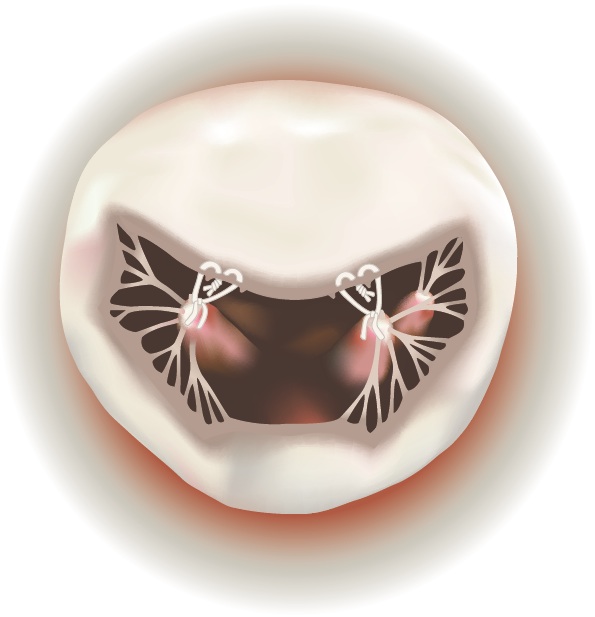

The mitral valve consists of two leaflets, supported by chordae and papillary muscles, and located between the left atrium and left ventricle of the heart. The mitral valve prevents blood from leaking back into the lungs when the heart contracts. When the valve fails, patients may be severely affected.

Degenerative mitral valve disease is a common disorder affecting around 2% of the population. Common findings include a “prolapse” ( slipping or falling our of place), due to elongation or rupture of the chordal apparatus. When the two leaflets fail to close tightly, the mitral valve becomes insufficient, sometimes allowing blood to leak back into the atrium from the ventricle.

A prolapse can occur on either the anterior (front) leaflet or the posterior (rear) leaflet. Usually, the annulus, where the leaflets attach, is also dilated or enlarged.

| Mitral Valve Prolapse on Anterior Leaflet | Mitral Valve Prolapse on Posterior Leaflet |